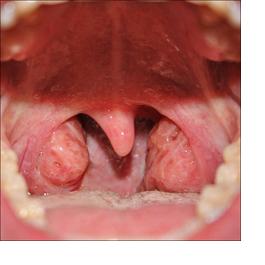

As amígdalas são duas estruturas redondas que ficam no fundo da boca (uma de cada lado). Elas em geral são visíveis quando nos olhamos no espelho com a boca bem aberta e a língua para fora ou com a boca aberta e a língua comprimida pelo dedo ou uma colher.

Em algumas crianças, o tamanho exagerado (hipertrofia) das amígdalas causa problemas de saúde. Em outras, apesar de um tamanho próximo ao normal, as amígdalas inflamam com muita frequência.